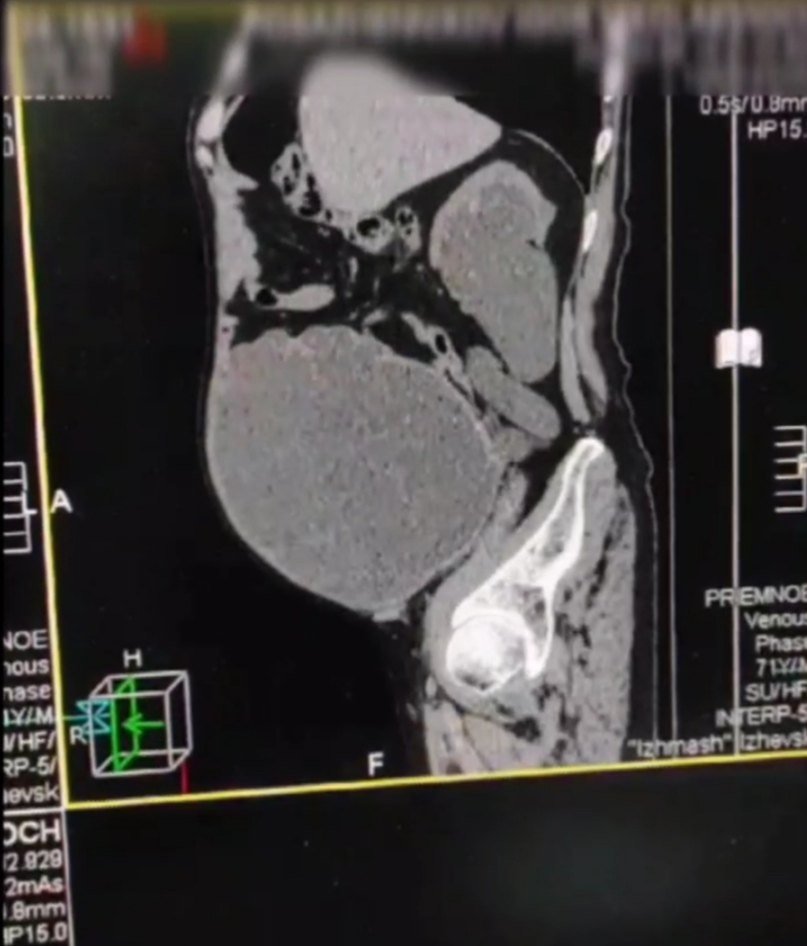

Ижевск, Удмуртия. Врачи городской клинической больницы №6 Ижевска оказали помощь пациенту с дивертикулом мочевого пузыря, в котором долгое время скапливалась моча. Об этом сообщается на официальной странице больницы «ВКонтакте».

Дивертикул мочевого пузыря сформировался у пациента за несколько лет. Невнимательность к своему здоровью довела человека до опасного состояния. В мочевом пузыре начала скапливаться моча, а необходимость постоянного натуживания спровоцировала постепенное ослабление и растяжение стенки органа.

В результате мочевой пузырь занял большую часть брюшной полости. Врачи урологического отделения ГКБ №6 поставили уретральный катетер и вывели 9 литров мочи. Затем была установлена цистома.